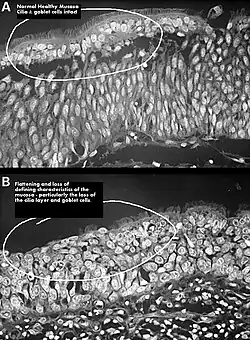

Squamous metaplasia of nasal respiratory epithelium.

One possible cause may be changes to the nasal mucous membrane and to the nerve endings in the mucosa resulting from chronic changes to the temperature and humidity of the air flowing inside the nose, caused in turn by removal or reduction of the turbinates.[3][7] The TRPM8 receptor, responsible for the sensation of nasal openness (patency), is activated by high-speed airflow, which cools the nasal lining through evaporation. This cooling triggers signals to the brain, making breathing feel easier. Nasal passage enlargement alters airflow, reducing turbulence and mucosal cooling which results in reduced sensation of airflow. Studies confirm that without the inferior turbinate, air conditioning in the nose is less effective.[7]